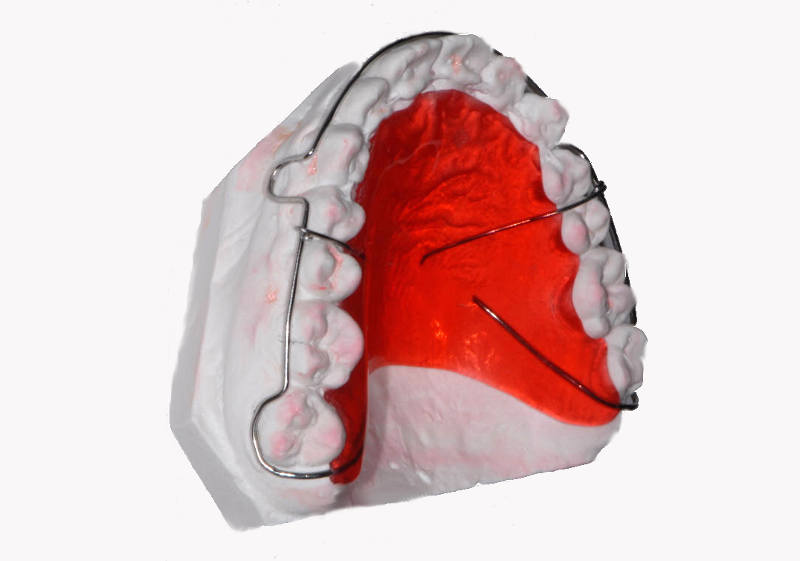

Alexanderplåt